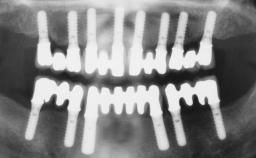

# of Implants 6

Type of Implants One-Piece

Defining Characteristics Fully edentulous upper jaw to be rehabilitated with four or more implants

Modality 6+ implants with immediate loading

Loading Protocol Immediate